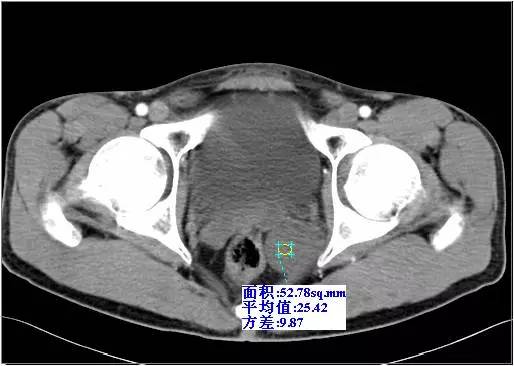

CT示左侧精囊区见一肿块,大小约4.3 cm×3.6 cm;平扫呈稍低密度(相对邻近肌肉密度),密度不均,其内可见散在分布更低密度区,CT值约18-28HU(图1),动脉期CT值20-28HU(图2),静脉期CT值20-30HU(图3),肿块边缘规整、边界清楚,与直肠膀胱分解清楚。

图1 CT平扫病灶呈稍低密度,边界清楚

图2 CT增强动脉期示病灶无强化

图3 CT增强静脉期示病灶无强化